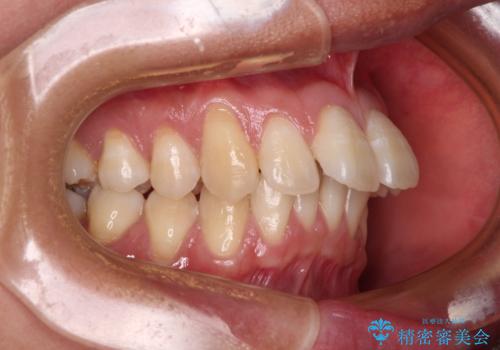

- 上顎前歯の突出感を気にして来院された患者様です。

舌の突出癖の影響で、歯列が前方に飛び出いた形態となっている状態でした。

抜歯矯正とするような歯列ではないため、舌のトレーニングを行いながら歯列を側方に拡大させることで口元の突出感を改善することとしました。

横顔は元々突出した印象ではなかったのですが、上顎前歯の角度が改善したことで、唇の閉じにくさが改善されました。